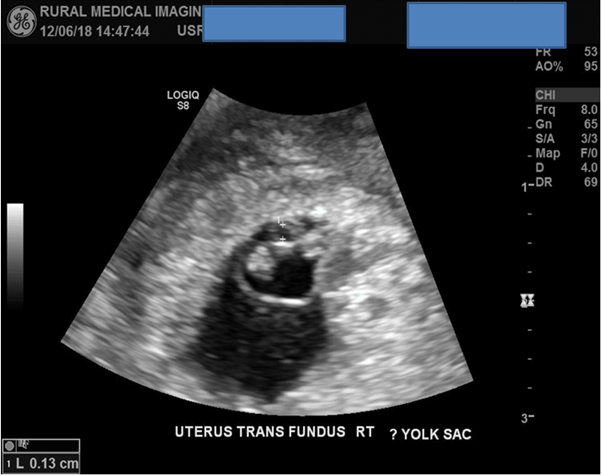

A superior scan in transverse plane of the right adnexa confirms the presence of a single GS with a possible internal foetus present. Although the initial first image was of suboptimal quality the HD zoom function was utilised for the next images for improved image optimisation and for confirmation of a possible live foetus. The angle of the TV probe was moved more inferiorly to place the pathology into the centre of the screen improving the FOV.

Figure 5: Initial images of a GS with a possible internal foetus are of suboptimal quality.

With the HD zoom function now enabled and an improved FOV multiple images of diagnostic quality were now acquired which confirmed that a right interstitial single EP was present. Three CRL’s were acquired totalling an average length of 7mm.